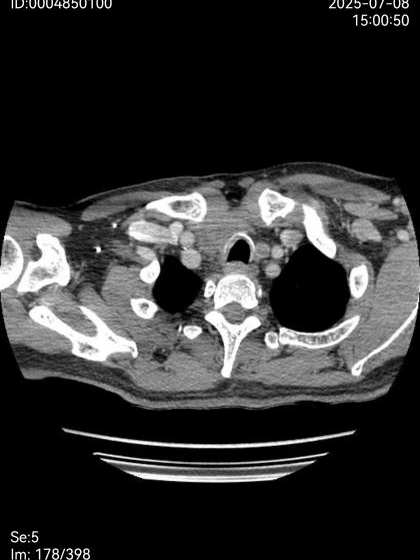

治疗前

治疗后

经过两个月的规范治疗,9月5日患者复查时,影像学检查显示肿瘤体明显,电子鼻咽喉镜证实气道通畅,赵龙珠主任团队为其拔除气管套管并封闭造瘘口,患者恢复自主呼吸。